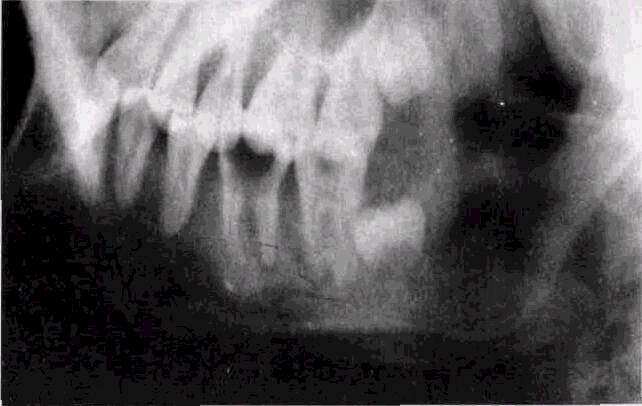

Рентгеновские снимки посттравматического остеомиелита челюсти: Медицинские случаи

Раздел: Образы вокруг